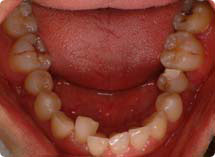

ÀÕ¸ö°ú ±³Á¤

HOME <°Ç°±³Á¤< 잇몸과 교정